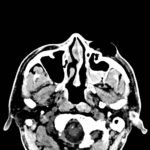

Physical exam showed marked left palpebral subcutaneous crepitus, as well as bulbar and palpebral conjunctival bulging. Visual acuity was normal with intact extraocular movements, and normal pupillary exam. Computed tomography (CT) imaging of the face was obtained and revealed multiple displaced fractures involving the left orbital floor and zygomatic arch associated with moderate periorbital and postseptal extraconal gas, resulting in orbital proptosis.